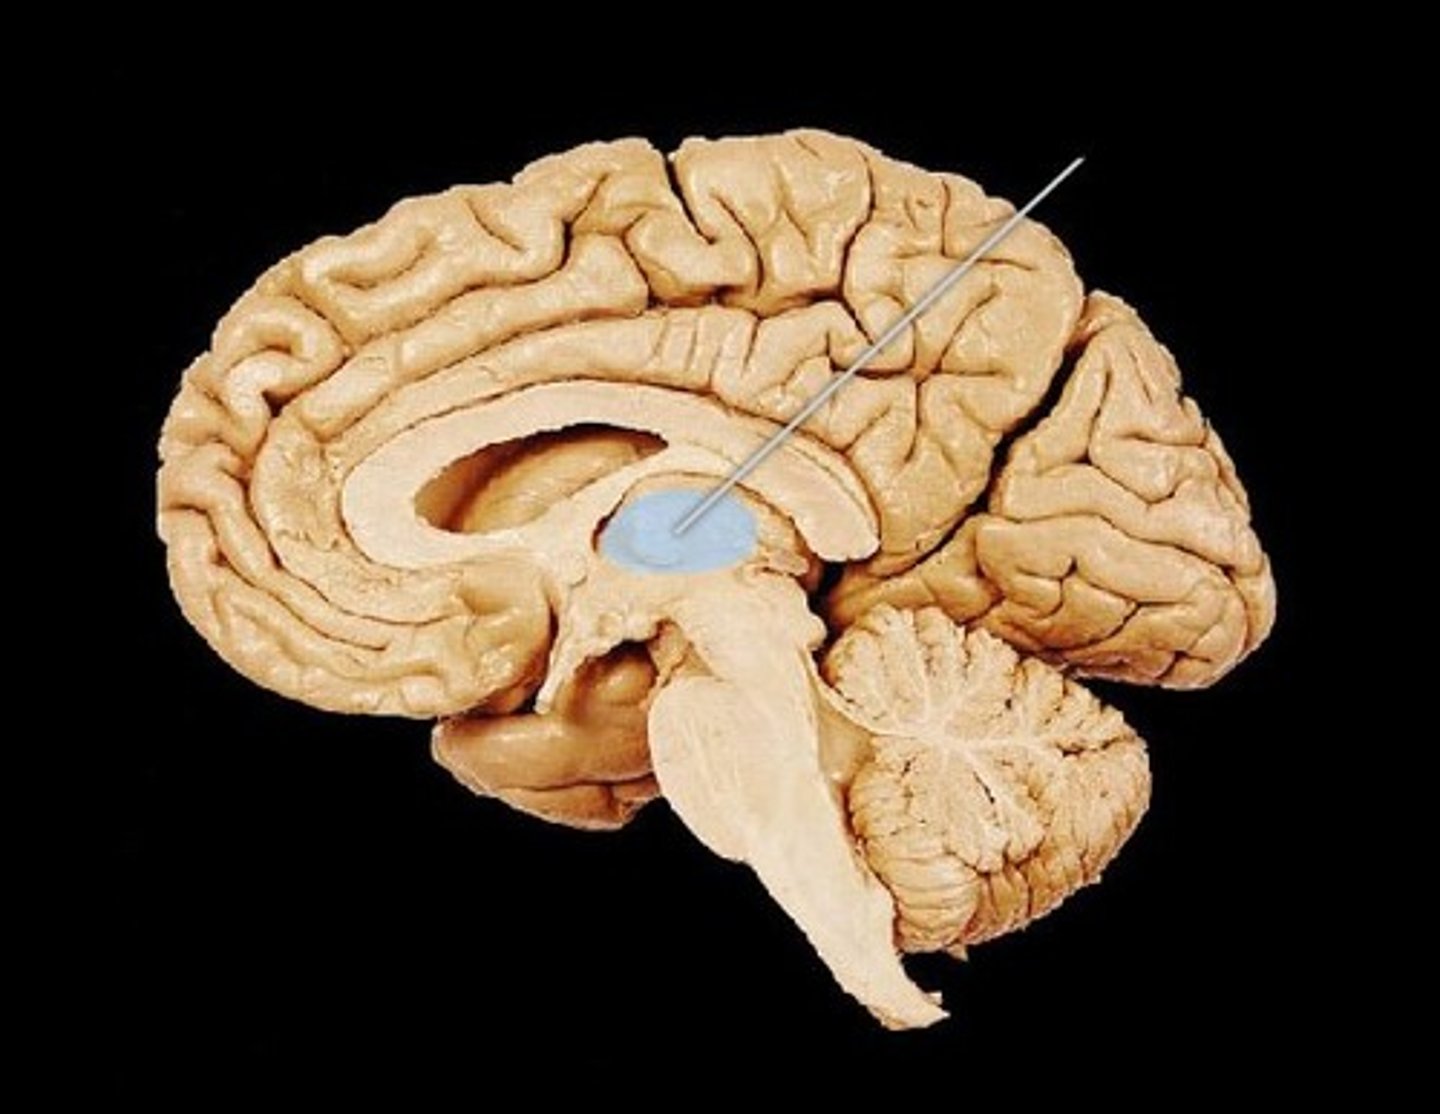

MIdsagittal View of brain

Lateral Ventricle

Third Ventricle

Cerebral Aqueduct

Forth Ventricle

Corpus Callosum

Fornix

Thalamus

Pineal Gland

Superior Colliculi

Inferior Colliculi

Midbrain

Hypothalamus

Cerebral Cortex Gray Matter (nerve cell bodies)

White Matter (myelinated nerve fibers)